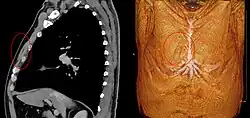

Musculus sternalis seen at axial CT and volume rendering.